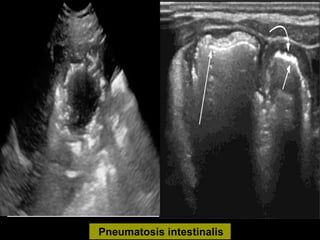

Pneumatosis intestinalis

Air within the portal venous system

Indirect evidence

 Pneumatosis intestinalis

 Air in portal venous system